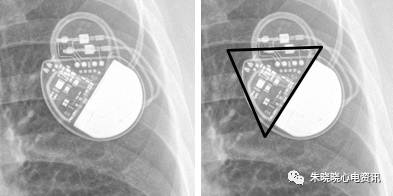

百多力起搏器看起来像鸟嘴(图5),

美敦力的Vitatron起搏器除外电池其余部分呈三角形(图7),

图5 百多力起搏器

图7 美敦力公司Vitatron起搏器